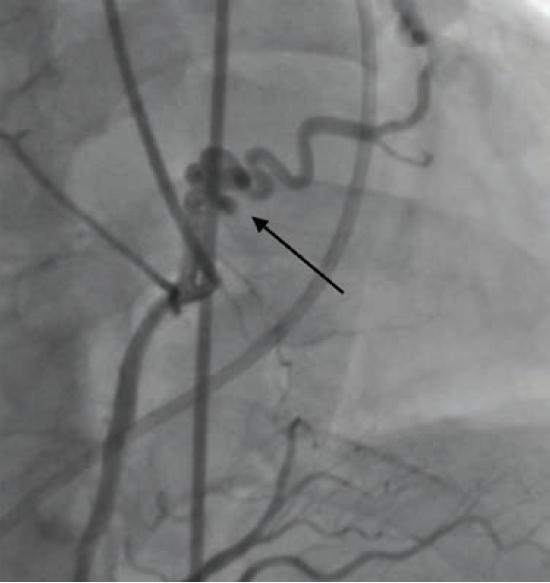

Cardiac catheterization revealed fistulae from the RCA to the pulmonary artery (PA) (Figure 2) and from the LAD to the PA, diffuse CAD, and a giant coronary artery aneurysm as previously described (Figure 3). The aneurysm demonstrated complex web-like vasculature extending towards the aortic root, across the right ventricular outflow tract, and into the proximal PA, with one large vessel connecting with the proximal RCA. The pulmonary-to-systemic flow ratio (Qp/Qs) was 1.14, indicating insignificant shunting, and cardiac index was normal.

He was scheduled for catheter-based closure of the coronary artery aneurysm; however, at the time of intervention, the aneurysm was suspected to have thrombosed due to competing flow following bypass graft surgery. Ascertained on fluoroscopy during left heart catheterization, the RCA-to-PA CAF demonstrated limited flow, while the LAD-to-PA CAF demonstrated partial flow. Repeat CCTA confirmed thrombosis of the coronary artery aneurysm without residual communication to the PA. The patient reported improved exercise capacity and no further cardiopulmonary symptoms.